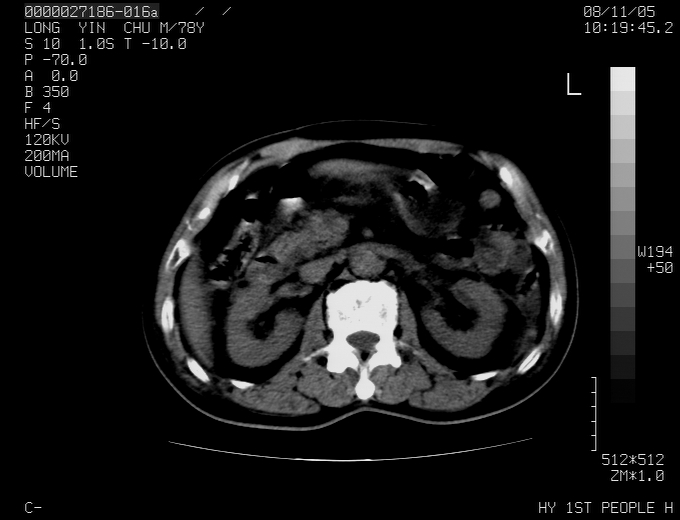

标题: CT16532:M78Y,肝脏病变,请会诊 [打印本页]

标题: CT16532:M78Y,肝脏病变,请会诊

腹胀,腹痛就诊,男性,78岁,外院b超未见异常。

肝ca,脾肾转移

支持脾肾转移瘤,双侧胸腔积液。

考虑弥漫性肝癌并脾及双肾转移.双侧胸水.

图片质量欠佳:多考虑:左侧肾癌。脾脏转移!胸膜转移!

肝脾肾转移瘤可能性大,左肾不除外梗塞,双侧胸水

考虑弥漫性肝癌并脾及双肾转移,双侧胸水。

考虑肝癌并双肾及脾脏转移;双侧胸腔积液。